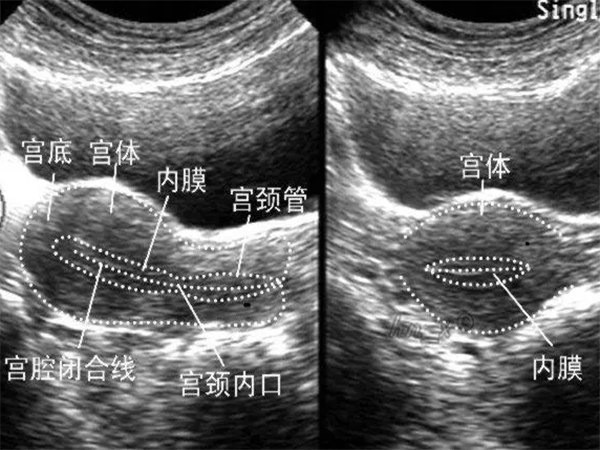

在婦科檢查中,子宮內膜厚度是一個重要的指標,它關係到女性的生育能力和健康狀況,很對女性對此也是十分的重視,但女性不同情況下的子宮內膜厚度是不一樣的。

對於育齡期女性,內膜厚度為7mm表示處於月經增生期,在之後的一週左右就會發生排卵,排卵日前後同房會增加受孕的機率,因此可選擇在此後的一週左右同房來增加受孕機率。同時,如果想要確定身體是否排卵,可使用排卵試紙進行監測。

如果絕經或更年期女性子宮內膜7mm,那麼考慮是不正常的。如果伴隨著下腹部疼痛、發熱、異常陰道分泌物或陰道出血的症狀,可能是出現了子宮內膜炎,可以去醫院進行血常規、B超等方面的檢查,明確診斷。